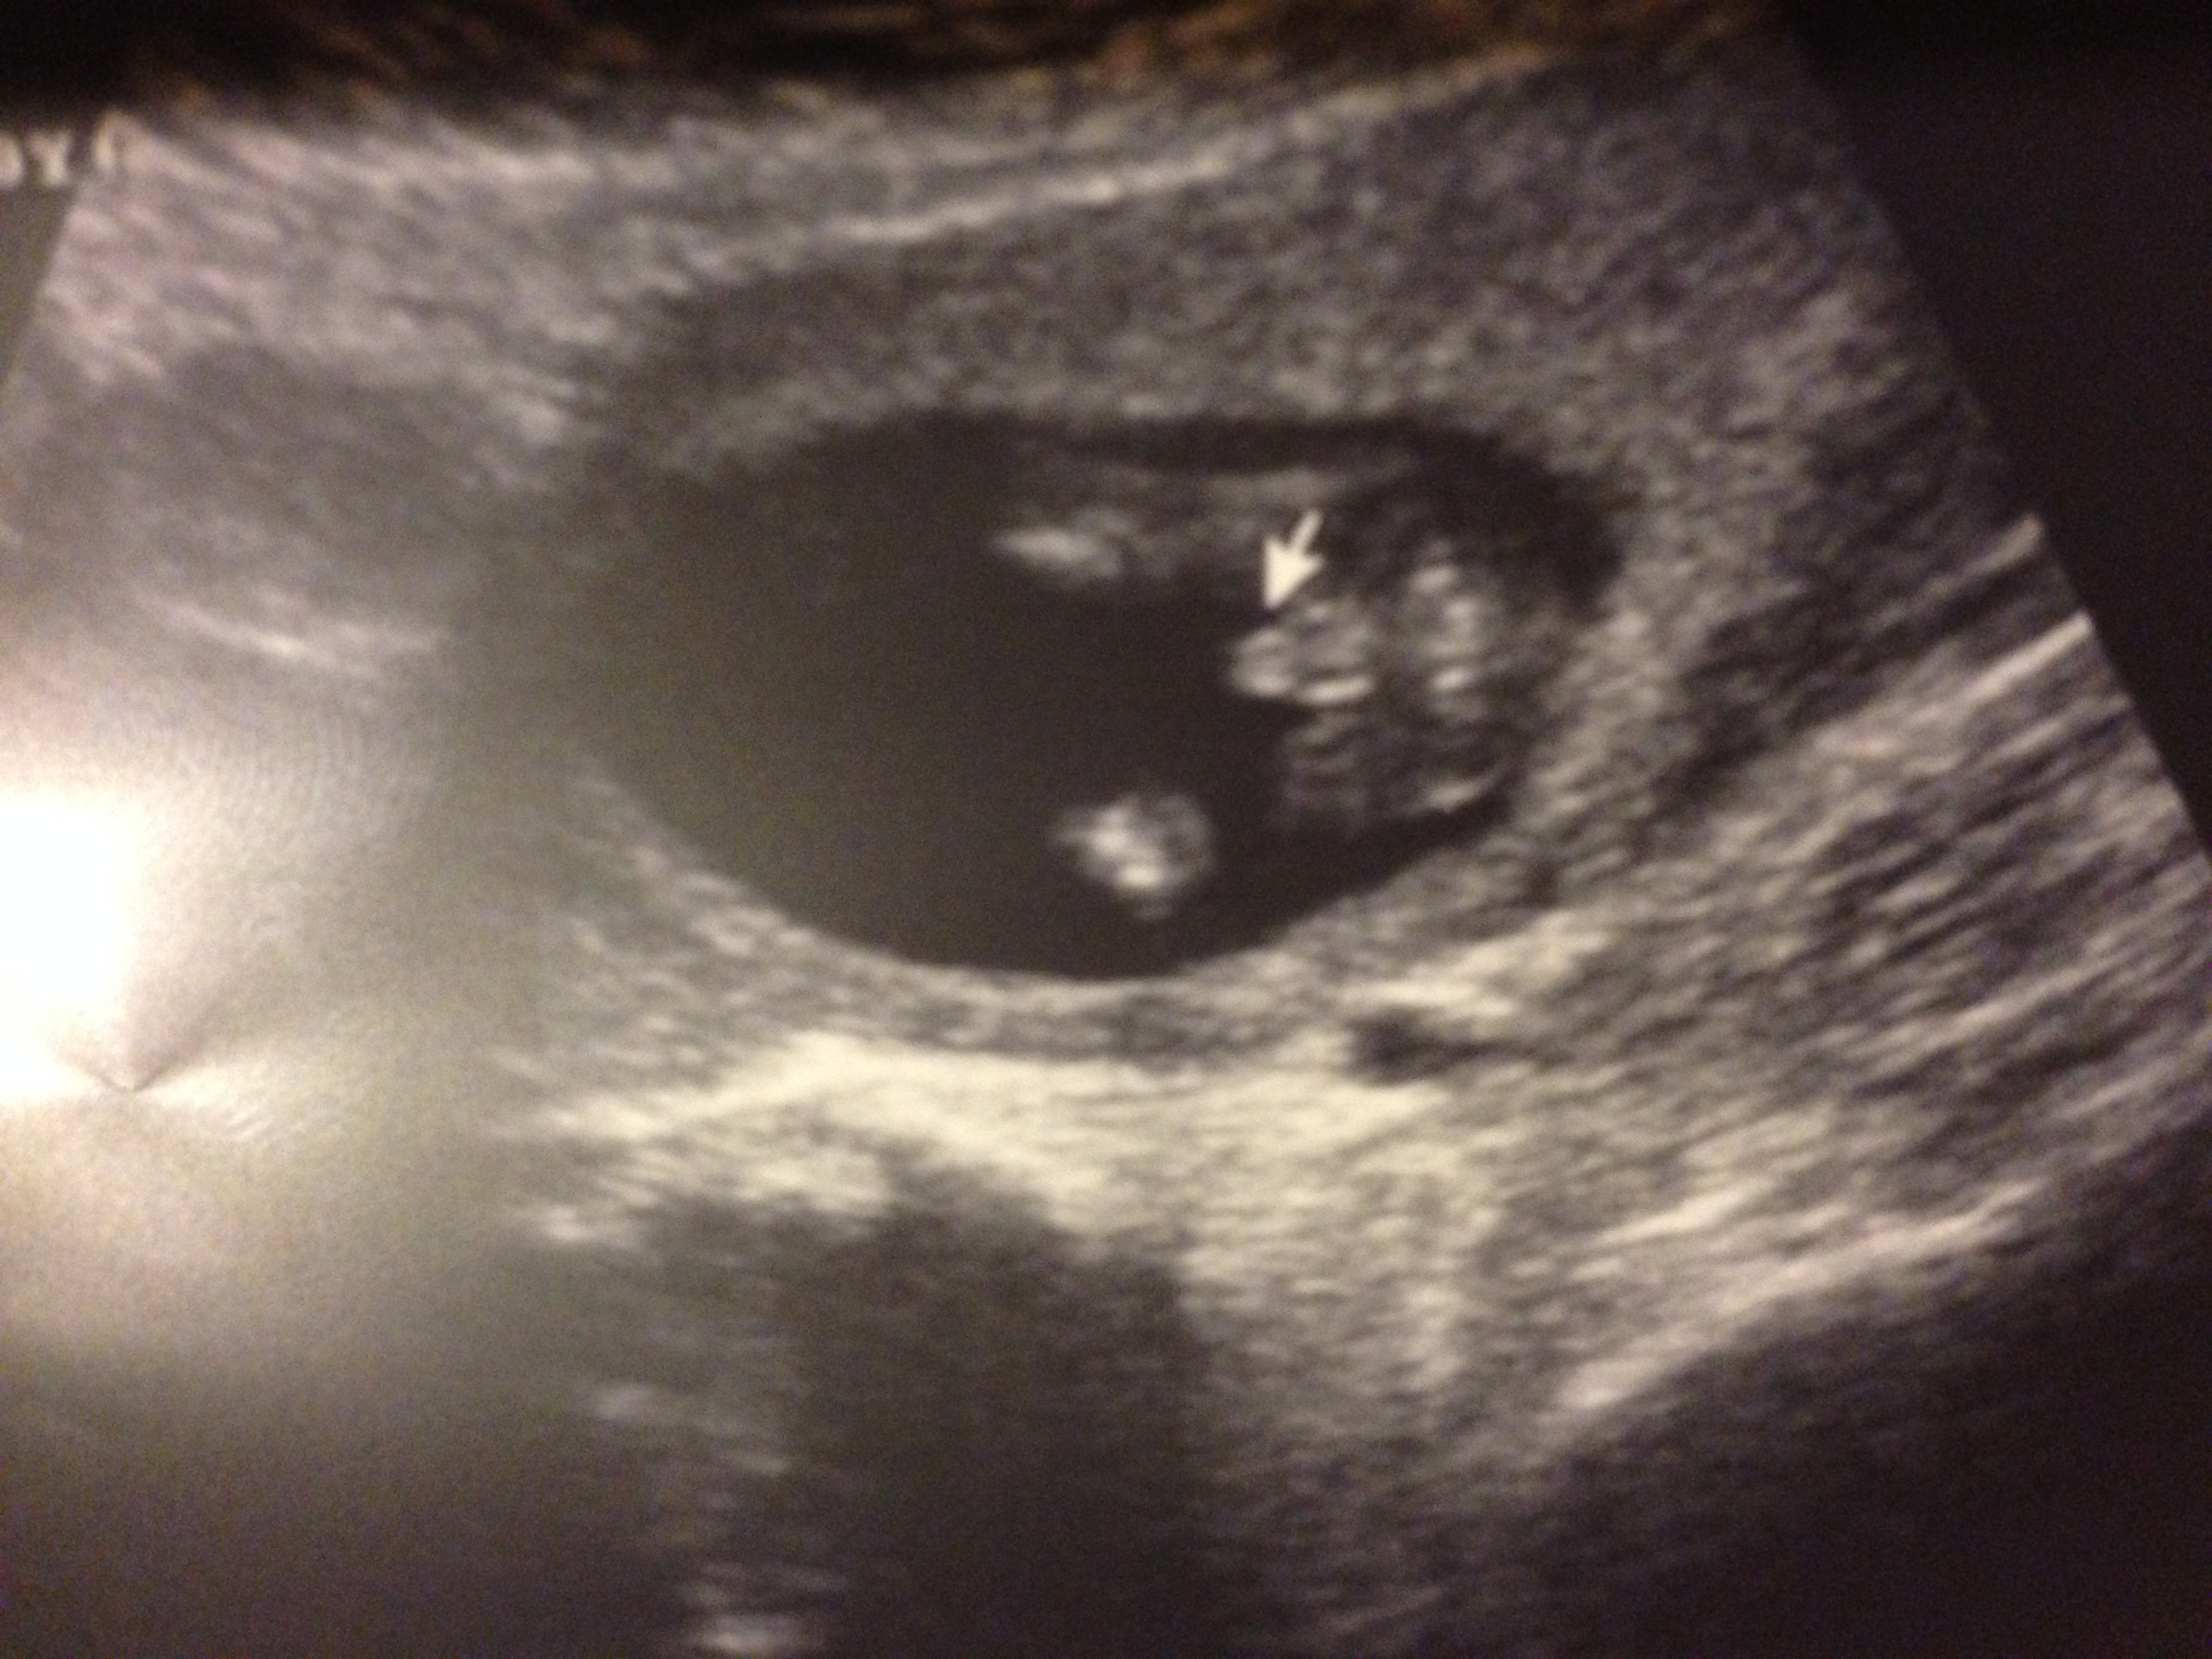

14 week 6 day potty shot!!

Attachment 15001

Congrats on your boy...

Congrats again :)